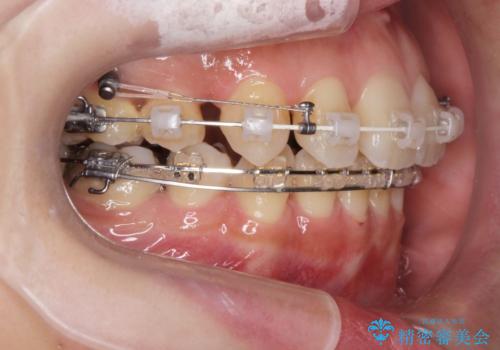

八重歯を矯正治療で治したい!

- 八重歯・がたつきのある歯並びの改善を求めて来院されました。

全部の歯が入り切るスペースがなかったため、小臼歯4本を抜去しワイヤーを用いたマルチブラケット矯正を選択しました。

歯並びの改善と共に、歯ブラシがしやすくなった!と喜んでいただくことができました。